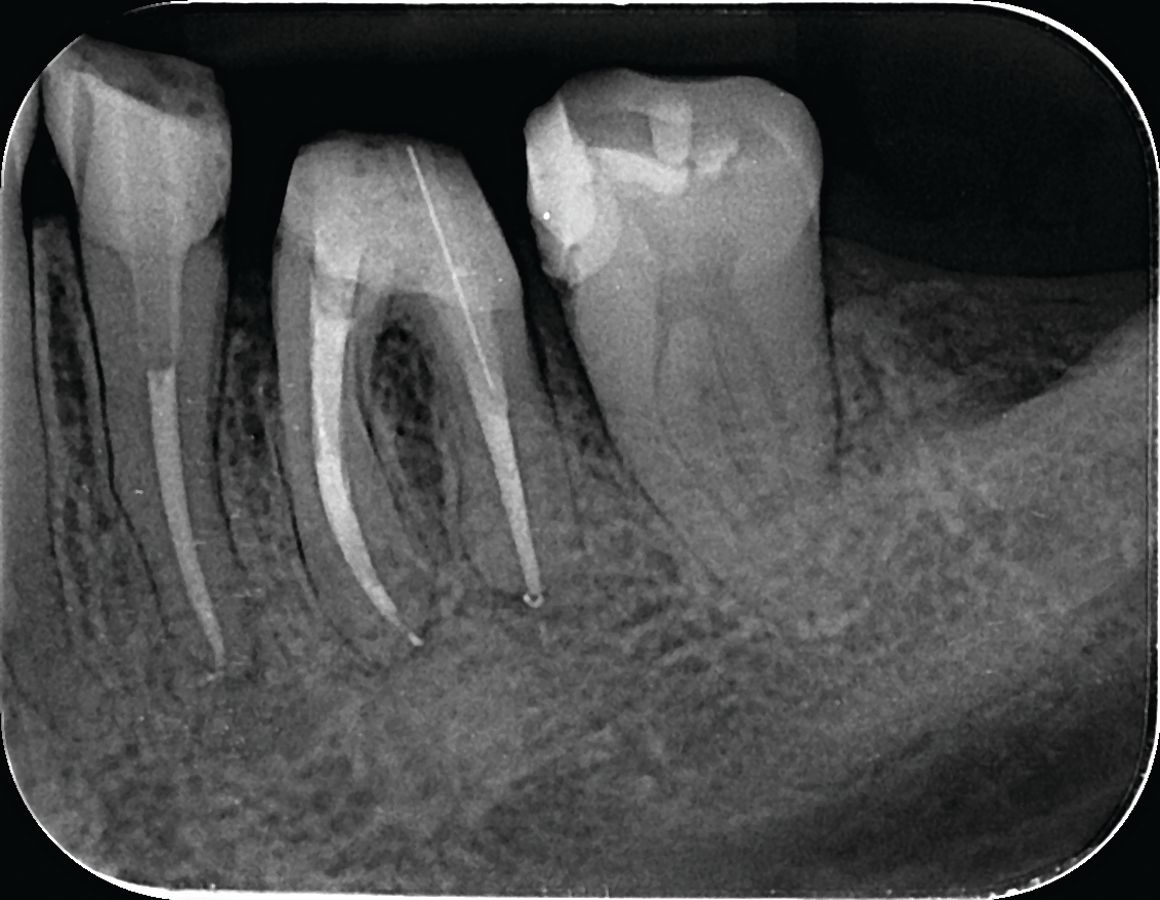

The final x-ray shows the completed root canal treatment, restored subgingival distal carious lesion, and glass-fiber post (Figure 8).

Figure 8. After completion of root canal treatment, repair of subgingival carious lesion, core buildup and glass fiber post in distal root of tooth #19, in preparation for permanent crown.